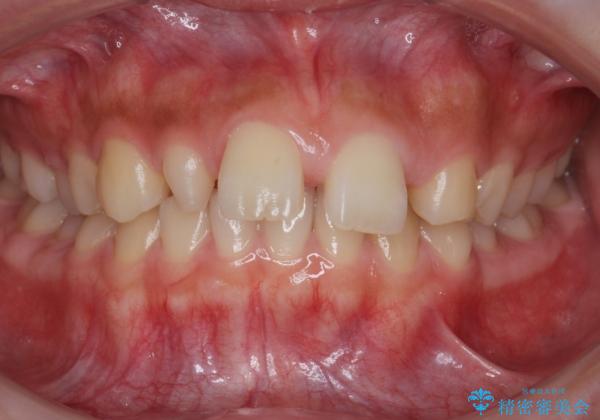

前歯が出っ歯ですきっ歯 抜かずに前歯を見た目良く

今回は左右とも1歯対2歯の関係であるため、それは変えずに前歯を可及的にひっこめて足りない部分をブリッジで補う治療としました。

矯正後の前歯ブリッジについては横浜桜木町歯科の大元院長が担当しています。

奥歯の関係を完全に1級にするには右上の小臼歯の抜歯が必要でしたが、もともと左上の前歯が生まれつき少ないため今回は歯を抜かずに治療しています。